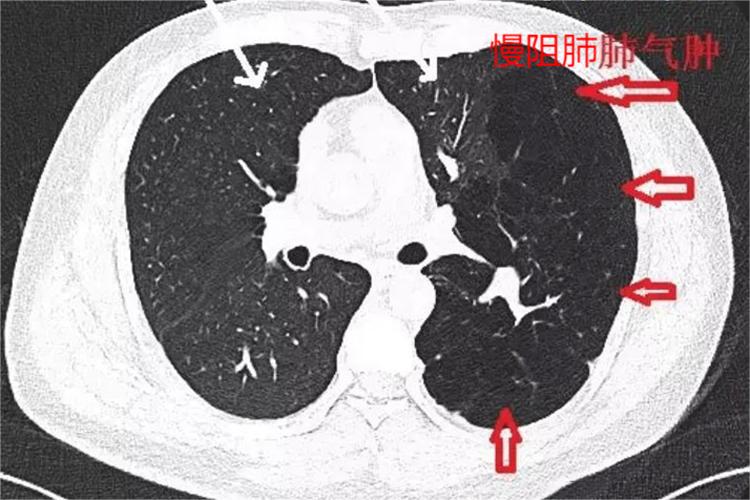

慢阻肺即慢性阻塞性肺疾病,肺部CT上可见低密度的肺泡腔、肺大疱与肺血管减少,并可区别小叶中心型肺气肿,全小叶型肺气肿或隔旁肺气肿。除肺部CT显示信息外,亦可见慢性咳嗽、咳黏液性痰液、气短、呼吸困难、喘息和胸闷、胸廓形状改变、缩唇呼吸等临床表现。